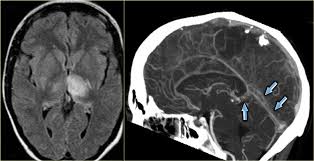

Common subtypes include transverse sinus thrombosis and superior sagittal sinus. What causes cerebral venous sinus thrombosis? Magnetic resonance imaging of cerebral venous sinus thrombosis. Aha scientific statements ⅲ venous thrombosis ⅲ sinus thrombosis, intracranial ⅲ brain infarction figure 1. Cerebral venous sinus thrombosis in early pregnancy: The cavernous sinus is one of the several cerebral veins and cavernous sinus thrombosis is a specific type of cerebral venous (sinus) thrombosis. Cerebral venous thrombosis (cvt) or cerebral venous sinus thrombosis (cvst): Cochrane database syst rev 2011; Cerebral venous and sinus thrombosis (cvst) is a rare disease responsible for less than 1% from the total of avc causes (bajenaru, 2010). Thrombosis of cerebral veins and venous sinuses is a rare disease, which accounts for less than 1% of all cases of stroke. The venous circulation of the brain is done. Risk factors, presentation, diagnosis and outcome. See that article for a discussion of that specific clinical entity.

Magnetic resonance imaging of cerebral venous sinus thrombosis. (iii) clinical and radiological features of brain lesions in csvt compared with arterial stroke, and (iv) a low threshold for ct or mr venography in children with acute neurological symptoms is essential. Can cerebral venous sinus thrombosis be prevented? Thrombosis of cerebral veins and venous sinuses is a rare disease, which accounts for less than 1% of all cases of stroke. Cerebral venous thrombosis (cvt) is an uncommon disorder in the general population. A thrombotic obstruction of the cerebral veins and/or related anatomical structures (dural sinuses) which drain blood from the brain. Cerebral venous thrombosis accounts for less than 1 % of all cases of stroke worldwide. A case report and review of the literature. Cerebral venous and sinus thrombosis (cvst) is a rare disease responsible for less than 1% from the total of avc causes (bajenaru, 2010). Cerebral venous sinus thrombosis occurs when a blood clot forms in the brain's venous sinuses. Cerebral venous thrombosis (cvt) refers to occlusion of venous channels in the cranial cavity, including dural venous thrombosis, cortical vein although not used routinely in clinical practice, whole brain ct perfusion may assist in establishing the diagnosis of cvt by detecting perfusion. Common subtypes include transverse sinus thrombosis and superior sagittal sinus. Cerebral venous thrombosis (cvt) or cerebral venous sinus thrombosis (cvst):